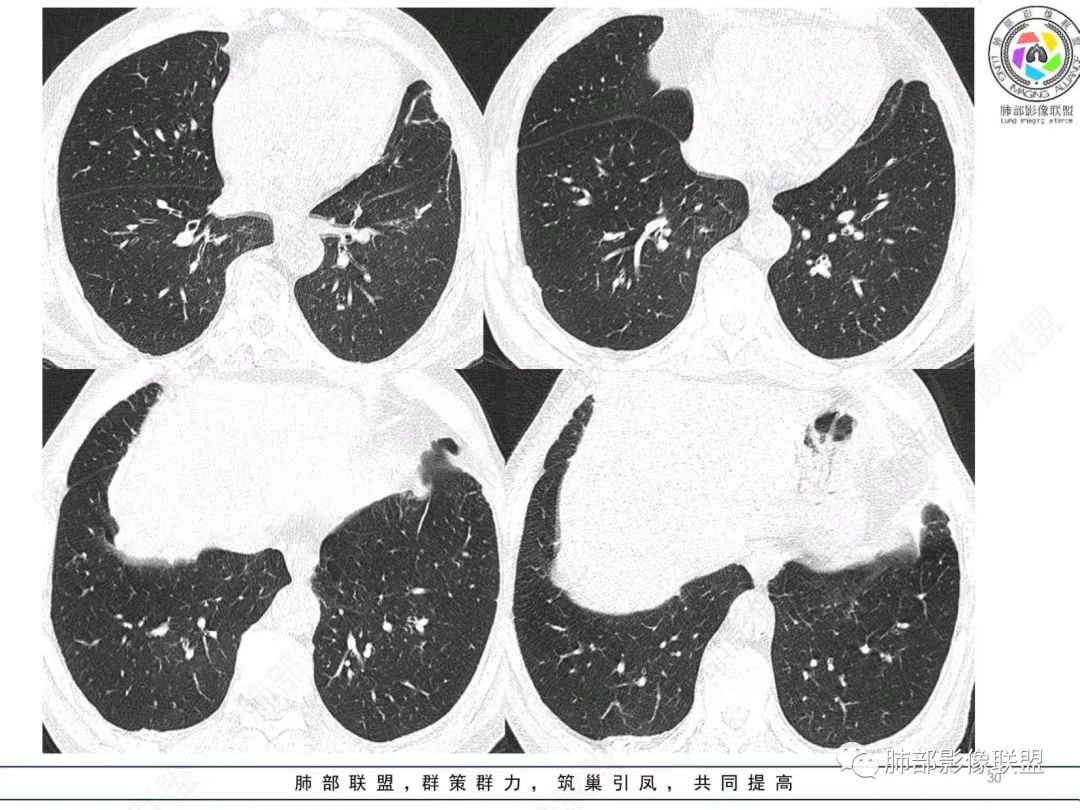

左肺胸膜下巨大占位,跨叶裂,宽基底与胸膜相连,胸膜钙化,平扫密度较低,强化不明显,可见内部血管显影,支气管充气征和扩张,考虑为恶性,倾向于淋巴瘤

左侧胸腔巨大肿块,跨叶生长,临近胸膜钙化,边缘模糊,可见支气管影,定位肺内,增强后轻度强化,边缘见血管影,考虑淋巴瘤,鉴别肉瘤

我要修正一下观点了:仔细看了视频,肿块占位效应明显,对周围血管,支气管有推挤,增强后强化不明显,NSE增高,半年体重下降25公斤,虽然有内部支气管扩张,血管漂浮,边界清楚支持淋巴瘤,但强化太低,膨隆,占位推挤太明显(淋巴瘤一般没有这么明显的占位效应),胸膜关系有载桩,恶病质明显(乏力,半年体重下降了25公斤),NSE也明显增高,就不支持淋巴瘤了。还是考虑外朝内的恶性肿瘤,间质来源的肉瘤伴有神经内分泌分化或者大神泌。

不支持淋巴瘤的有四点:1、对周围血管支气管推挤明显。2、胸膜有栽桩,3、强化太弱(淋巴瘤一般还是中度以上甚至高度强化多见),4、NSE升高明显,体重下降太明显。

左肺紧贴胸膜巨大肿块,跨叶裂生长,密度均匀,边缘清晰,内支气管略扩张,增强见血管影,强化不明显,胸膜栽赃,钙化,考虑淋巴瘤。

1)部位:周围型或中央型软组织肿块,以周围型为多见,且肿瘤多位于肺上叶。如本例:该肿瘤位于左肺上叶。

2)大小及形态:由于本病恶性程度高,早期症状不明显,发现时肿块均较大。如本例病变巨大。

3)肿块边界和边缘:多较清楚,呈圆形、类圆形,且由于肿块生长速度不均匀,可见分叶,毛刺少见。有报道肿块周围毛玻璃影是多形性癌特征表现。

4)密度:肿块平扫为软组织密度,由于体积较大,内部常见大片状坏死,可出现不规则厚壁空洞或坏死内多发无壁小空洞,坏死多不均匀:坏死灶内可见如柳絮样的斑片样强化灶,坏死边缘与非坏死区分界不清本例坏死较明显,密度不均匀。

5)肿瘤强化方式:肺部恶性肿瘤强化程度与其血供丰富程度相关,血供丰富多强化明显,反之则较差。由于PSC 周边实性部分富血供及内部黏液变性、坏死,增强后肿块多数呈轻-中度边缘环形强化或不均匀小斑片状强化。国外学者对照病理发现肿瘤细胞或胶原组织增强扫描时强化,无强化的低密度区代表了黏液样变性区和出血坏死区。